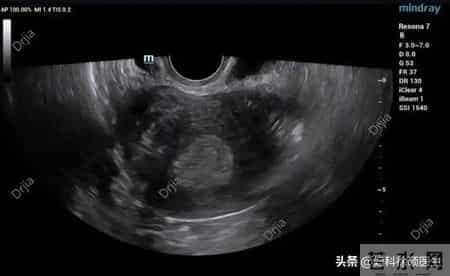

举个例子:小李的案例。她32岁,内膜一直偏厚,B超显示“不均质回声”。我问她:“最近是不是总熬夜?”她愣住:“医生,你怎么知道?我确实最近工作忙,天天凌晨睡……”长期熬夜会扰乱下丘脑-垂体-卵巢轴,让雌激素“失控”,内膜自然“疯长”。